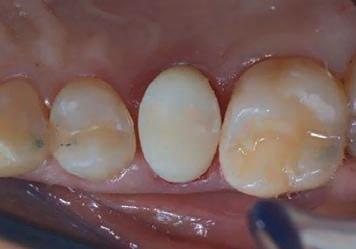

The canal was sealed with a Thermafil™ cone (Dentsply Sirona) with an apical diameter of 0.30 mm (Figs. 3-4).

Figure 3: Root canal therapy completed under proper isolation. Figure 4: Radiography of completed root canal therapy and reconstruction made completely in glass hybrid cement.